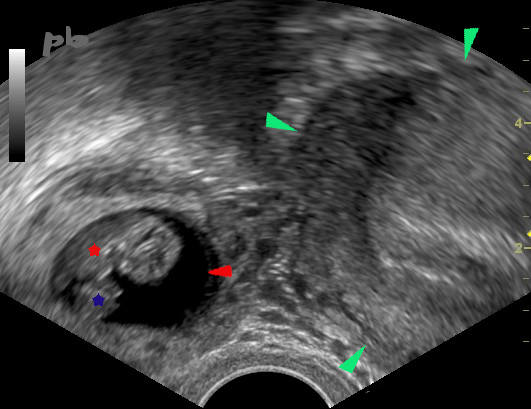

19- GEU droite

Petit sac gestationnel de 9 mm (entre les croix) accolé à l’ovaire droit (►).

Corps jaune (►).

19- Right ectopic pregnancy

Small 9 mm gestational sac (between crosses) attached to the right ovary (►).

Corpus luteum (►).